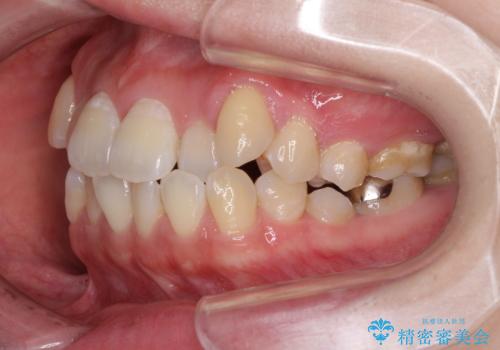

口元の突出感を改善 インビザラインによる非抜歯矯正

- 前歯がデコボコした上に口元が閉じにくいことを気にして来院された患者様です。

IPR(歯と歯の間を削る)と側方拡大では口の閉じにくさは改善できそうになく、一方で抜歯矯正を行うほどの突出感は認められませんでした。

親知らずを全て抜去し、歯列全体を後方に移動させることで口元の閉じにくさいを改善していくこととしました。

インビザラインでの歯列全体の後方移動は時間がかかりますが、しっかりと装着時間を守っていただいたので、スッキリとした口元に仕上げることができました。